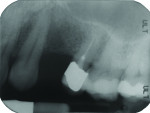

The patient had his upper left first premolar extracted approximately 5 years ago. There was buccal bone resorption (Figure 1) and a distance of 7 mm between the canine and the second premolar (Figure 2). After evaluation and consultation, the patient elected to have an MDI inserted and restored immediately with a full-crown restoration.